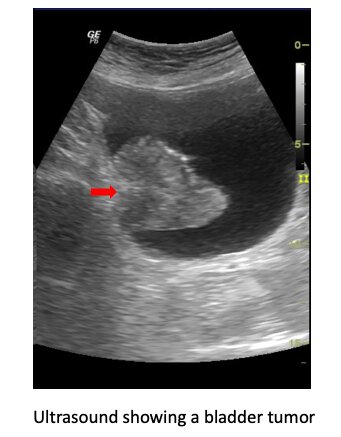

Bladder cancer is one of the most common urologic cancers. It usually presents with blood in the urine.

Imaging studies like a CT scan, or cystoscopy may reveal a bladder tumor. This needs to be removed and send for biopsy to determine its type, grade and extent.

This procedure is known as a transurethral resection of bladder tumor (TURBT) or bladder biopsy.